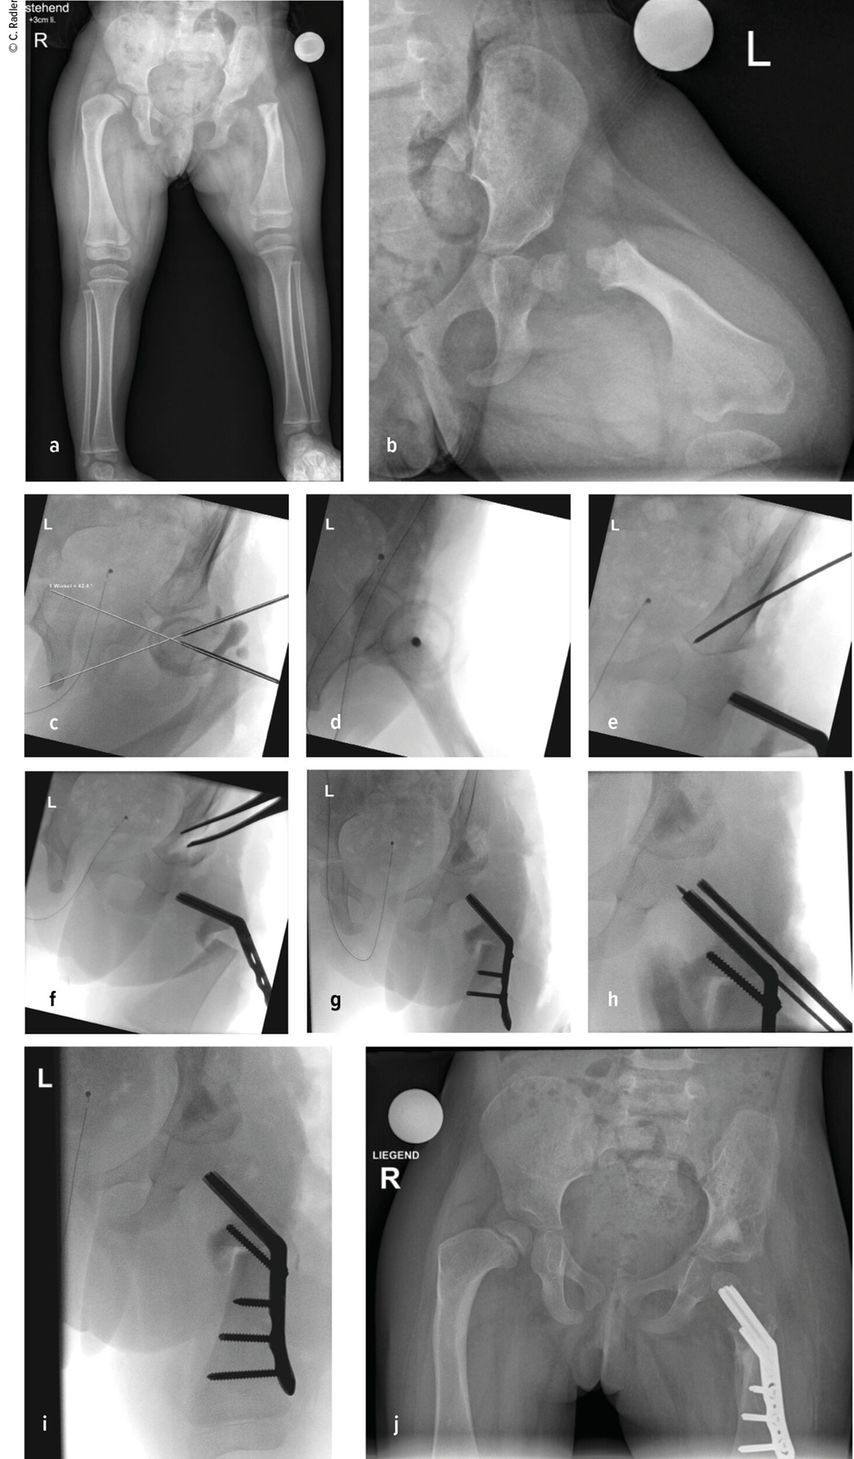

Milde Formen – Typ 1A – zeigen oft nur einen leichten Schenkelhalsvarus und eine verminderte femorale Antetorsion beziehungsweise Retroversion zusätzlich zur Verkürzung. Oft zeigt sich bei diesem Typ auch eine milde subtrochantäre Varusstellung und Sklerose. Mit zunehmendem Schweregrad addiert sich eine azetabuläre Dysplasie, wobei besonders die obere und hintere Überdachung der Hüfte vermindert ist. Beim Typ 1A ist in seltenen Fällen keine vorbereitende Operation erforderlich, insbesondere wenn die Überdachung der Hüfte sehr gut ist und ein CE-Winkel von über 20 Grad vorliegt. Es kann dann direkt mit einer Verlängerung des Femurs begonnen werden. Je nach verwendeter OP-Technik können eine eventuell vorhandene Retroversion und Varusstellung im Rahmen der Verlängerungsoperation akut über eine zusätzliche proximale Osteotomie und Montage an den oberen Teil des Fixateurs adressiert werden. (Abb.1).

Abb. 1: Operative Versorgung eines CFD rechts mit Varusstellung an der Hüfte und subtrochantärer Sklerosierung

Im Rahmen dieser Operation können auch die Retrotorsion und der Schenkelhalsvarus korrigiert werden. Eine Verlängerung bei nicht optimal überdachter Hüfte führt meist zu einer Subluxation oder Luxation, was eine schwerwiegende Komplikation darstellt, die nur schwer und meist nicht folgenlos zu beheben ist. Auch bei älteren Patienten ist die Überdachung vor einer eventuellen Verlängerung zu überprüfen, wobei besonders ab dem 4. Lebensjahr eine Tripelosteotomie eine bessere Überdachung und Einstellung der Pfanne gegenüber einer Acetabuloplastik erlaubt (Abb.2).

Abb. 2:Versorgung eines kurzen Pfannendachs mittels Tripelosteotomie, um die Hüfte während der Verlängerung vor (Sub-)Luxation zu schützen

Der Typ 1B ist durch eine verzögerte Ossifikation/Pseudoarthrose subtrochantär oder im Schenkelhalsbereich charakterisiert, wobei auch ein kombinierter Typ mit Schenkelhals und subtrochantär verzögerter Ossifikation vorliegen kann. Klinisch imponiert neben der massiven Verkürzung die Außenrotations- und Beugekontraktur. In diesen Fällen ist eine komplexe Rekonstruktion, bestehend aus mehreren Schritten, erforderlich, die als Super-Hip-Operation subsumiert wird (Abb. 3).